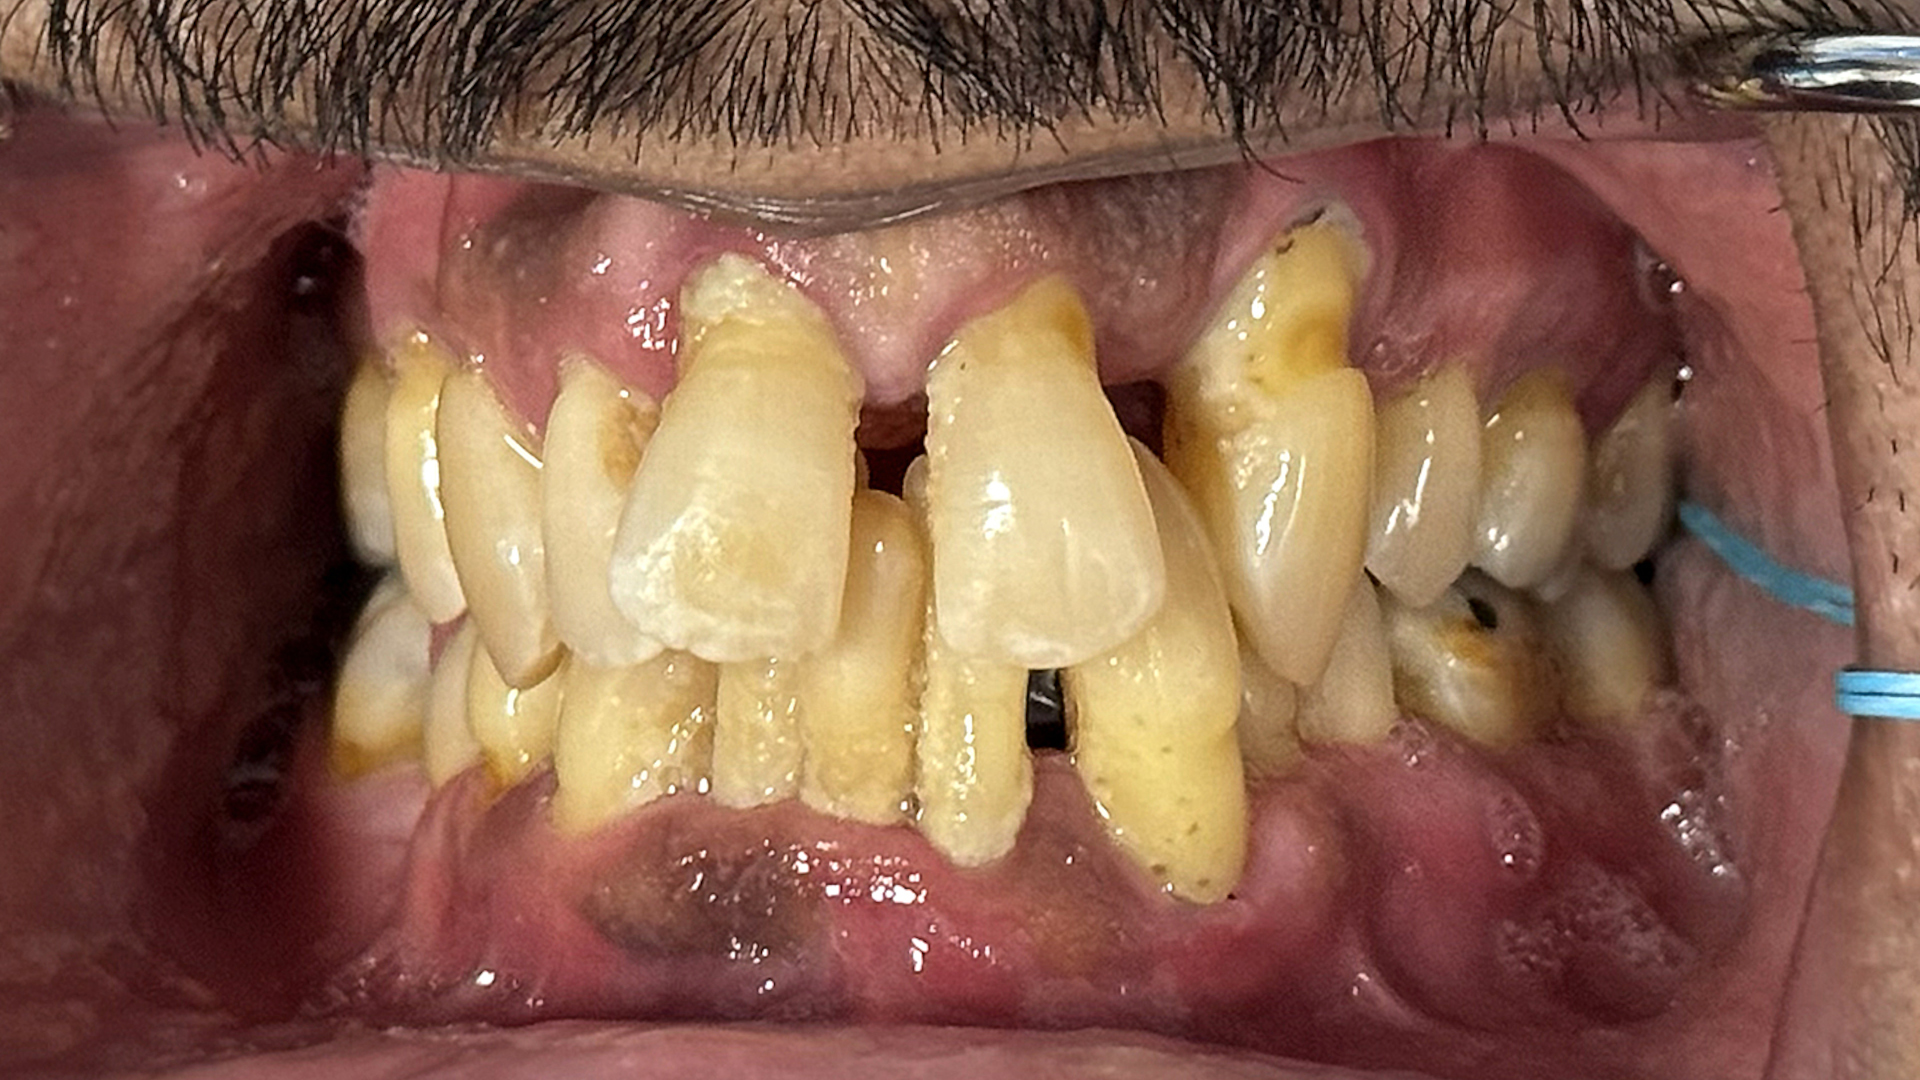

Fig. 1a: Pre-op situation. Intra-oral retracted view of the maxillary teeth, showing advanced periodontal disease and anterior spacing. (All images: Dr Scott D. Ganz)

Fig. 1b: Pre-op situation. Intra-oral retracted view of the maxillary and mandibular teeth in occlusion.

A 49-year-old male patient presented with failing maxillary and mandibular teeth. The findings of the clinical and radiographic examinations were severe periodontal disease, generalised bone loss, anterior spacing and tooth mobility, in addition to overall poor hygiene maintenance (Figs. 1a & b & 2a). The patient was informed of the findings, and several treatment options were discussed, including complete and/or partial dentures, implant-supported overdentures and implant-supported fixed restorations. After discussion regarding the options, the patient decided on full-arch implant-supported fixed restorations.